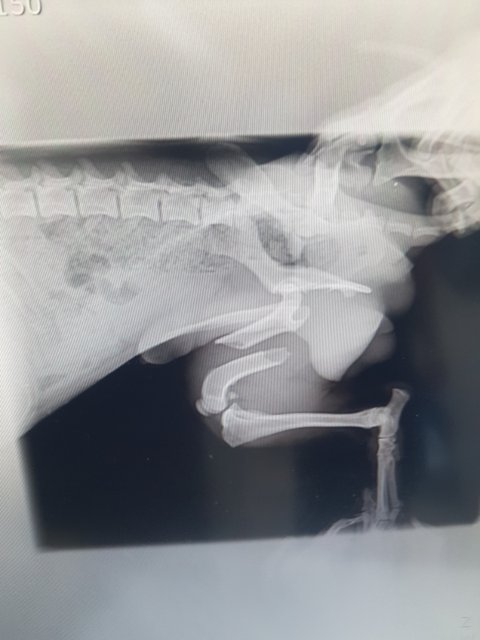

뒷다리골절과 사상충

대퇴부골절...

골절도 골절이지만 성충이 어마어마하게 많아 충을 꺼내는 수술을 해야할정도라고 합니다

부러진 다리 고통으로 아무것도 먹지를 못 하고 있습니다

수술을 해야하지만 마취위험이 높고 쇼크사도 될수있다고 합니다